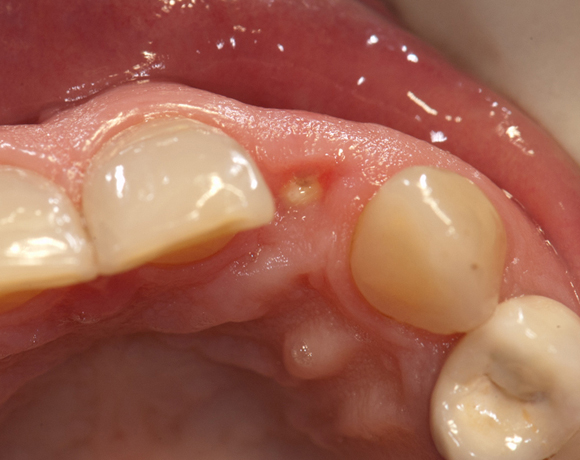

Im vorliegenden Patientenfall musste der Zahn 22 nach erfolgloser Endodontie entfernt werden. Die Nachbarzähne waren kariesfrei, es wurde eine Marylandbrücke (eine Brücke mit zwei Flügelchen, die palatinal an den Nachbarzähnen verklebt werden) oder ein Implantat besprochen. Die Patientin hat sich für ein Vollkeramikimplantat entschieden. In der Diashow wird der operative Eingriff bis zur fertigen Krone gezeigt. Die Einheilzeit betrug drei Monate.